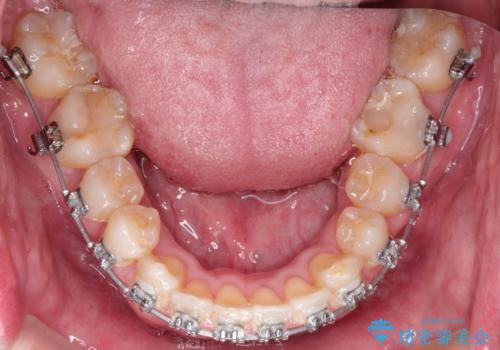

ワイヤーによる全体的ながたつきの矯正治療

- 30代男性

- メタル

- 1年3ヶ月

- 全体的ながたつきを治したいとのことで来院されました。

ワイヤー矯正とマウスピース矯正の二つの器具での治療をご案内し、ワイヤー矯正を選択されました。

インビザラインを装着するのがめんどうなので、ワイヤーの方があっているとのことで今回の治療方法を選択されました。